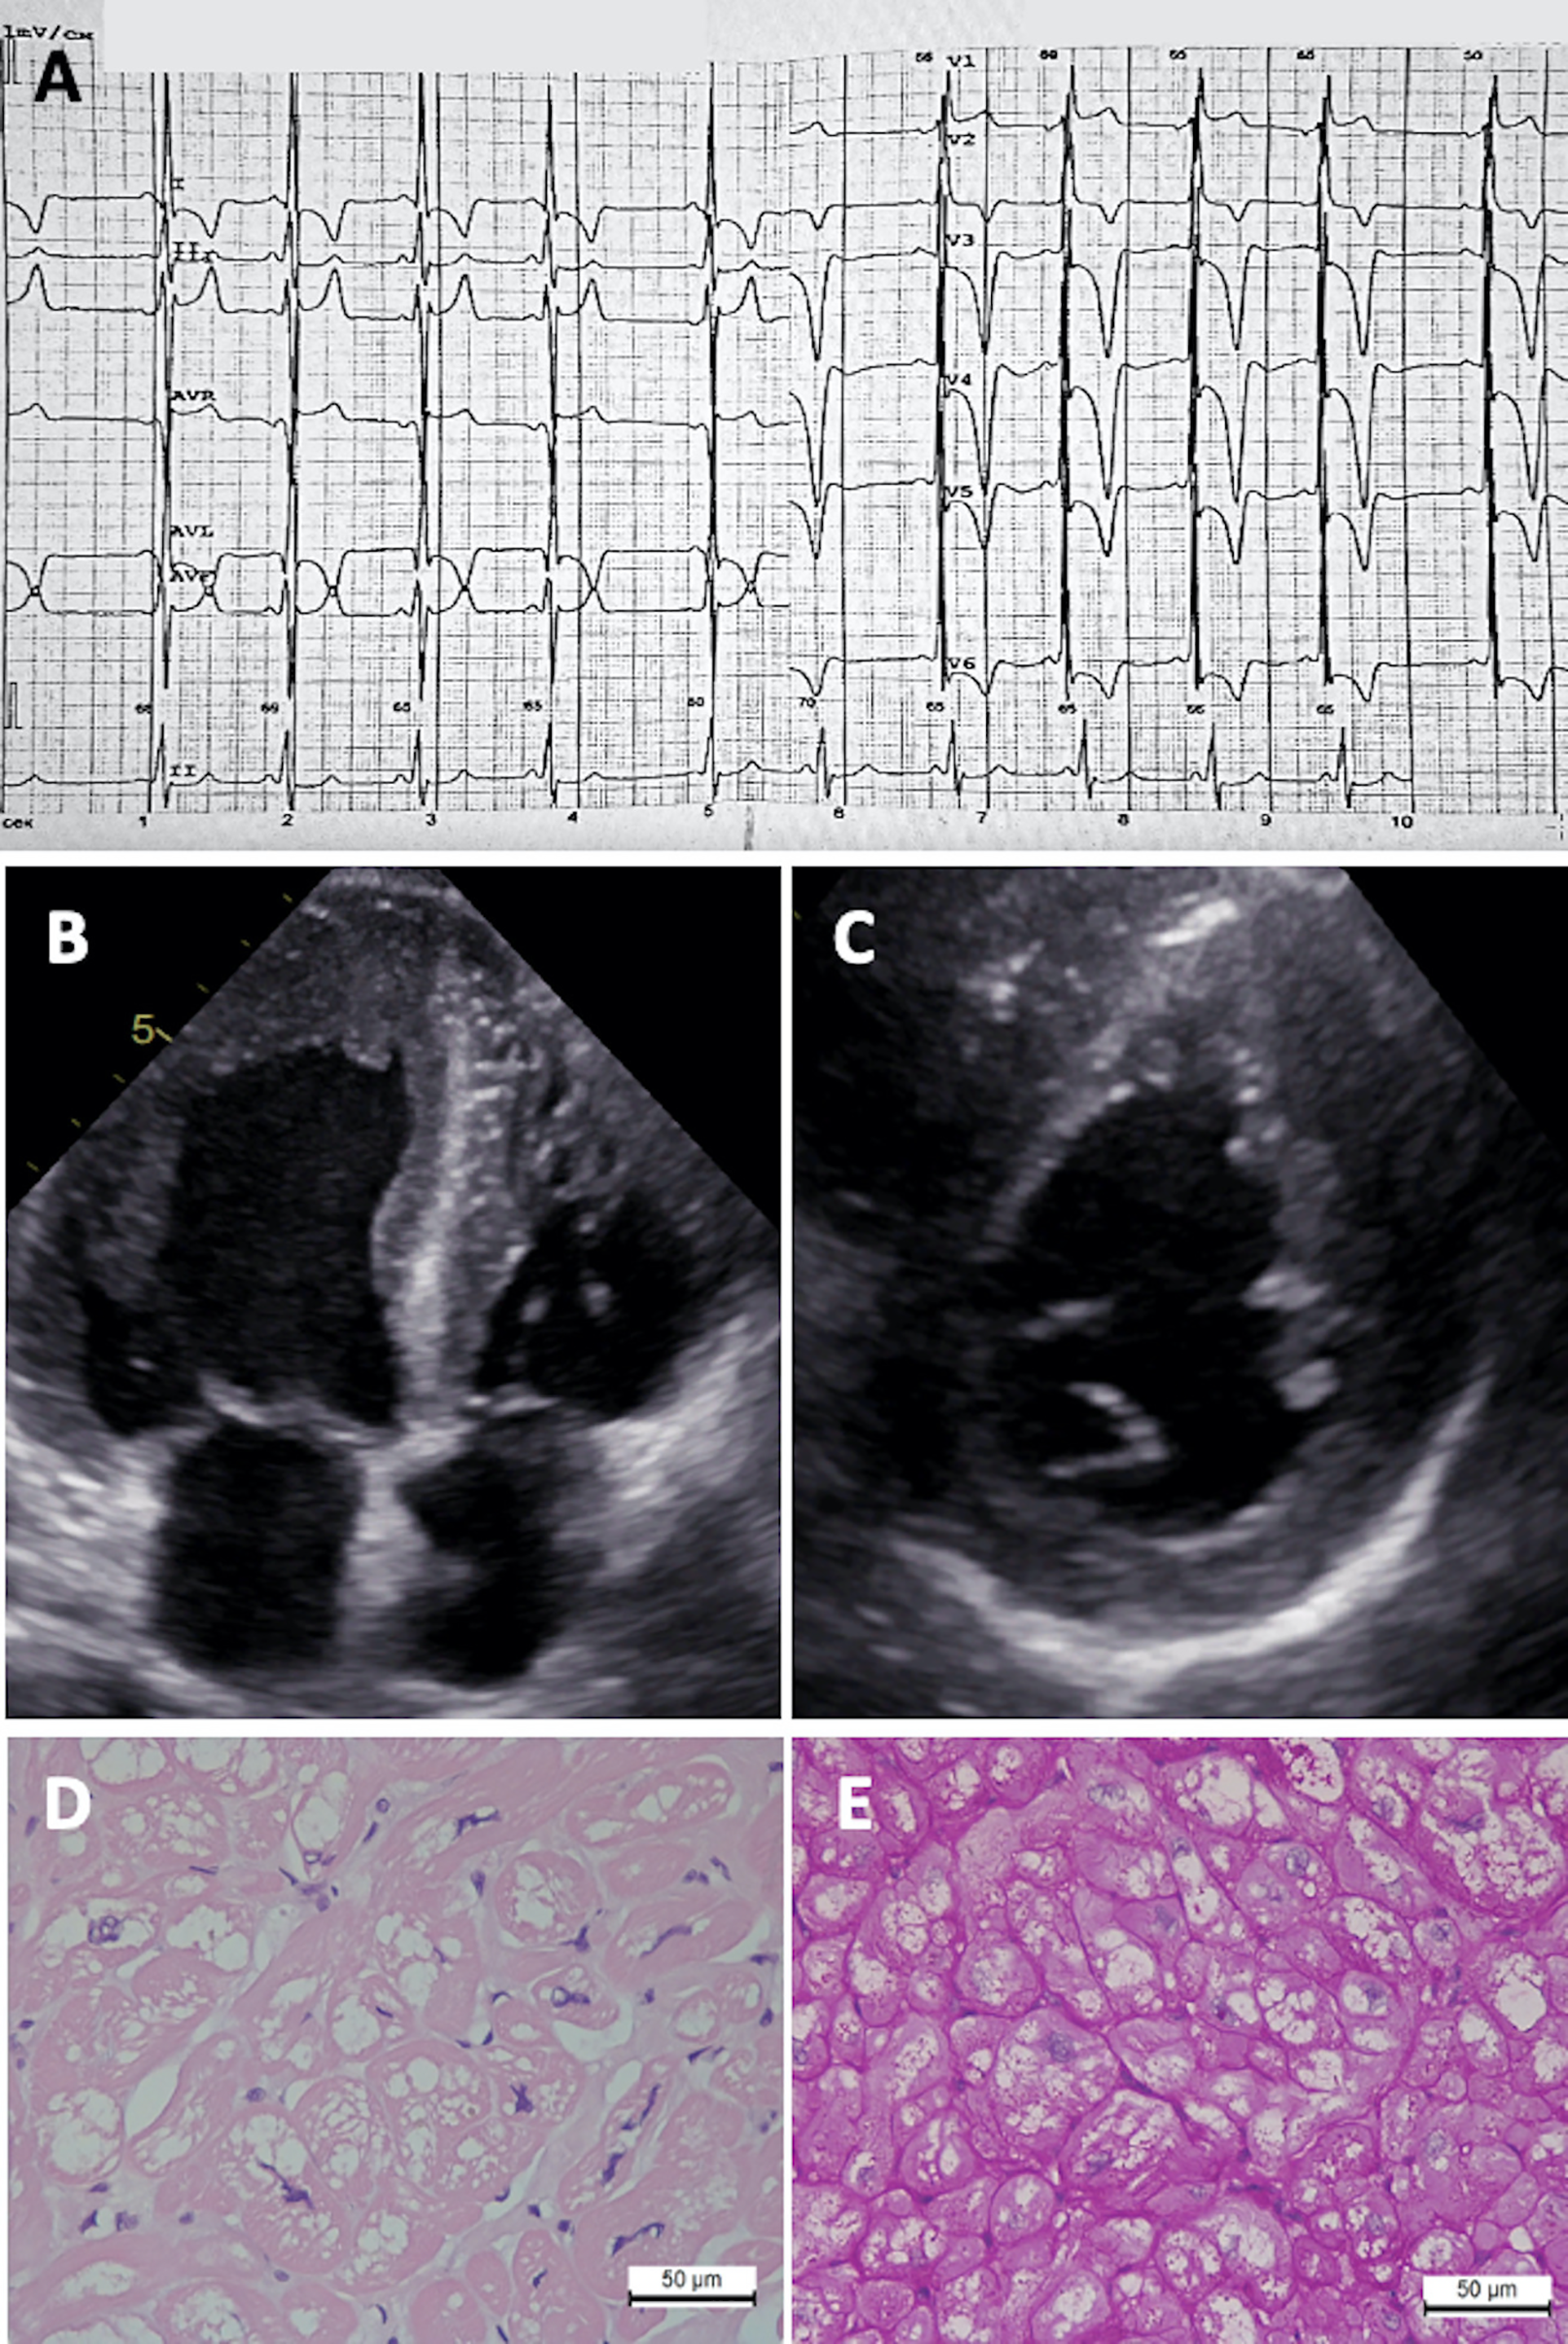

Figure 2

Diagnostic features of Fabry disease patient. (A) ECG showing LV hypertrophy, right bundle branch block, and giant T wave inversions. (B) 2D ECHO in apical four-chamber view and (C) short-axis view showing asymmetric concentric LV hypertrophy. Myocardial tissue revealing (D) cardiomyocyte hypertrophy and vacuolization (hematoxylin-eosin staining) and (E) PAS reaction.